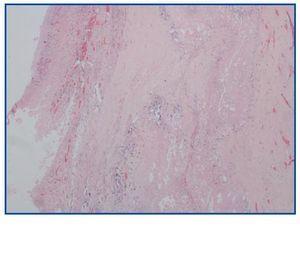

La necropsia demostró un proceso fibrosante sistémico (Figuras 1-4), con afectación de pelvis menor, retroperitoneo, en coraza alrededor de riñones, glándulas suprarrenales y páncreas, abarcando espacio periesplénico y perihepático; y mediastínico, en coraza alrededor de pericardio, arco aórtico y grandes vasos; y paquipleuritis derecha con fibrosis calcificada. Se apreciaron también: pancreatitis crónica fibrosa asociada, atrofia testicular, fenómenos de enfermedad aterombólica, hipertrofia ventricular izdª, y hepatopatía fibrosa crónica, en el contexto de un paciente con arteriosclerosis generalizada severa, con repercusión renal -nefroangiosclerosis bilateral con atrofia renal derecha, encefálica –infarto antiguo quístico izquierdo a nivel de ínsula-, y de colon –colitis isquémica rectosigmoide.

Figura 3.